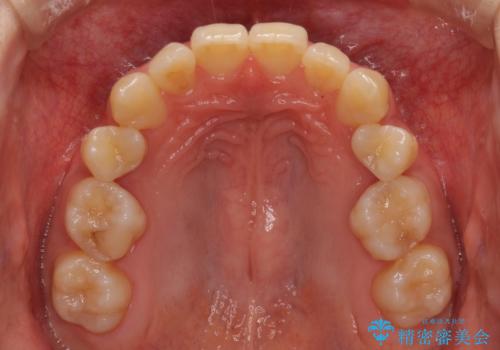

奥歯の反対咬合 上顎骨を拡大してインビザラインで矯正

- 奥歯の反対咬合を気にして来院された患者様です。

反対咬合は上顎骨の幅が下顎骨よりも小さいことが原因なので、拡大装置により骨幅を広げて上下関係を改善し、その後インビザラインにて歯並びを整えることとしました。

上顎骨を拡大したことで前歯に隙間ができ、1ヶ月ほど恥ずかしい時期がありましたが、しっかりとした咬み合わせに仕上がり、患者様には大変満足していただきました。